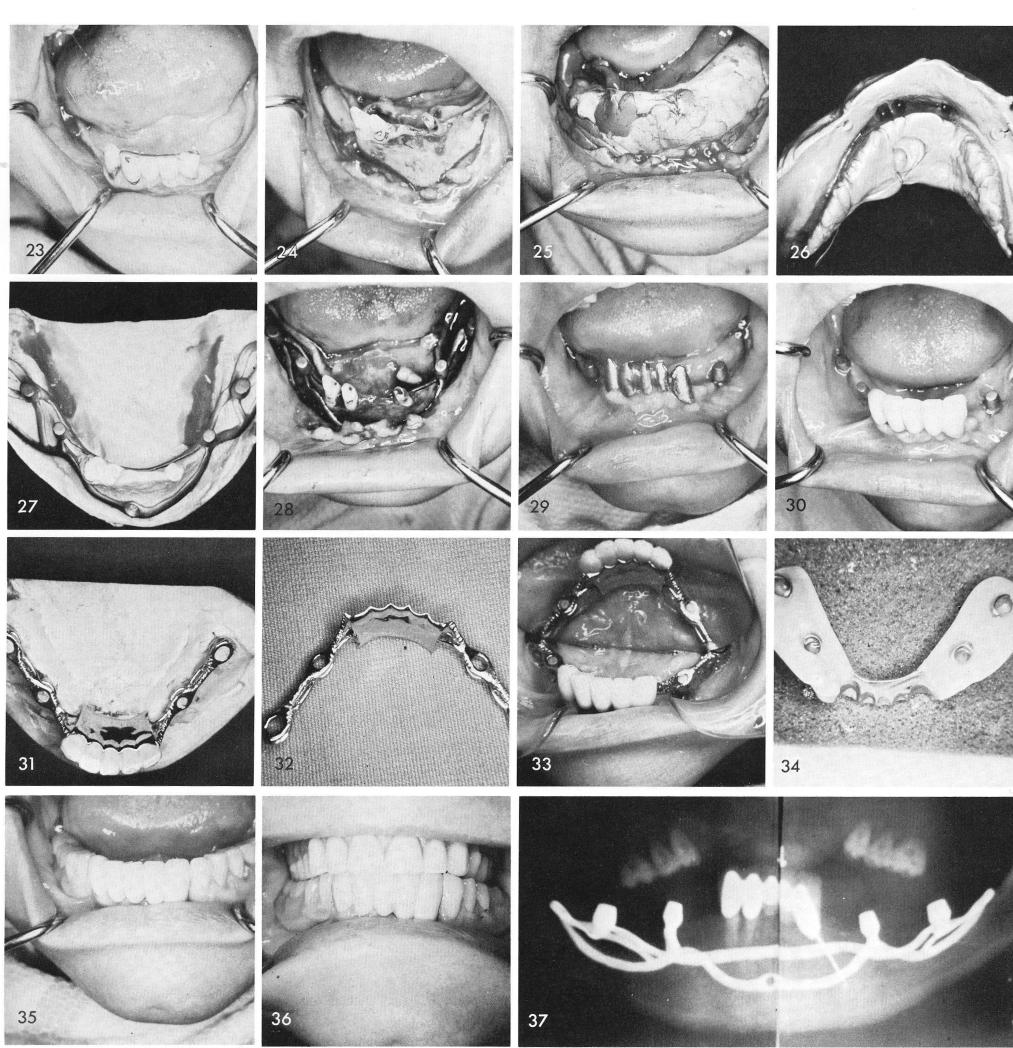

Another case showing some remaining well supported anterior teeth, fig. 23. The remaining teeth are prepared for full crown coverage restorations and the bone is recontoured to eliminate any infrabony pockets that may exist, fig. 24. Notice how little bone separates the left mental foramen from the resorbed crest and how much bone still exists anteriorly. The impression is taken, figs. 25, 26. The implant circumvents the remaining teeth, fig. 27. It is fitted in position, fig. 28. The healed tissues, fig. 29. The anterior teeth in this case were processed with a porcelain splint and a Kennedy type partial denture framework was cast to further support the anterior teeth and anchor on to the four subperiosteal implant posts, figs. 30, 31, 32, 33. After the case

1 Mental foramen lies close to the mandibular ridge crest